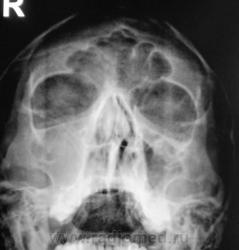

Пол пациента: Мужской пол Тип патологии: Другое Область исследования: Челюстно-лицевая область и шея Методы исследования: Rg Пациент направлен на рентгенографию придаточных полостей носа. Ваше мнение? https://radiomed.ru/sites/default/files/styles/case_slider_image/public/user/12/2..p8170059a.jpg?itok=7t4Nbh2k https://radiomed.ru/sites/default/files/styles/case_slider_image/public/user/12/3..p8170060.jpg?itok=IP4zEUbV https://radiomed.ru/sites/default/files/styles/case_slider_image/public/user/12/4..p8170060a.jpg?itok=H9fhfdKZ ID:5520 Ср, 18/08/2010 - 14:56 #1 Vikkur Не на сайте Был на сайте: 4 года 7 месяцев назад Зарегистрирован: 24.09.2009 - 14:34 Публикации: 1749 Мне видиться гиперпластический риносинуит, искривление носовой перегородки. причем спава практически тотальное затемнение.. Виктор. Ср, 18/08/2010 - 16:31 #2 Катенёв Валенти... Не на сайте Был на сайте: 7 лет 2 недели назад Зарегистрирован: 22.03.2008 - 22:15 Публикации: 54876 А, что по поводу нижнего края правой орбиты? У меня, что-то возникали сомнения, в "дефектности" этого контура. Ср, 18/08/2010 - 16:48 #3 Vikkur Не на сайте Был на сайте: 4 года 7 месяцев назад Зарегистрирован: 24.09.2009 - 14:34 Публикации: 1749 А есть ЛТ, потому что, я к своему стыду не вижу... Виктор. Ср, 18/08/2010 - 17:17 #4 Катенёв Валенти... Не на сайте Был на сайте: 7 лет 2 недели назад Зарегистрирован: 22.03.2008 - 22:15 Публикации: 54876 Есть. Сейчас выставлю. Ср, 18/08/2010 - 17:19 #5 Катенёв Валенти... Не на сайте Был на сайте: 7 лет 2 недели назад Зарегистрирован: 22.03.2008 - 22:15 Публикации: 54876 1 срез. Приложения: Ср, 18/08/2010 - 17:23 #6 Катенёв Валенти... Не на сайте Был на сайте: 7 лет 2 недели назад Зарегистрирован: 22.03.2008 - 22:15 Публикации: 54876 2 срез. Приложения: Ср, 18/08/2010 - 22:32 #7 Юрич Не на сайте Был на сайте: 6 лет 5 месяцев назад Зарегистрирован: 17.01.2010 - 09:55 Публикации: 351 я не вижу четко стенок в.челюстной пазухи справа - атрфия от давления? может мукоцеле? Чт, 19/08/2010 - 10:24 #8 Vikkur Не на сайте Был на сайте: 4 года 7 месяцев назад Зарегистрирован: 24.09.2009 - 14:34 Публикации: 1749 ассиметрия есть.. Виктор.

Мне видиться гиперпластический риносинуит, искривление носовой перегородки. причем спава практически тотальное затемнение..

А, что по поводу нижнего края правой орбиты? У меня, что-то возникали сомнения, в "дефектности" этого контура.

я не вижу четко стенок в.челюстной пазухи справа - атрфия от давления? может мукоцеле?